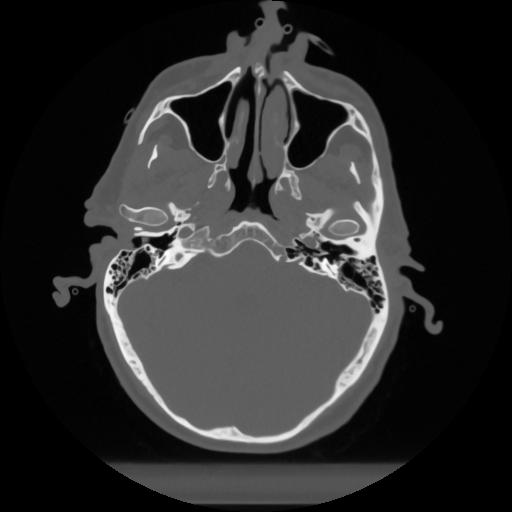

12 P.BLANDAS,,Vol,0.5,P.BLANDAS,,